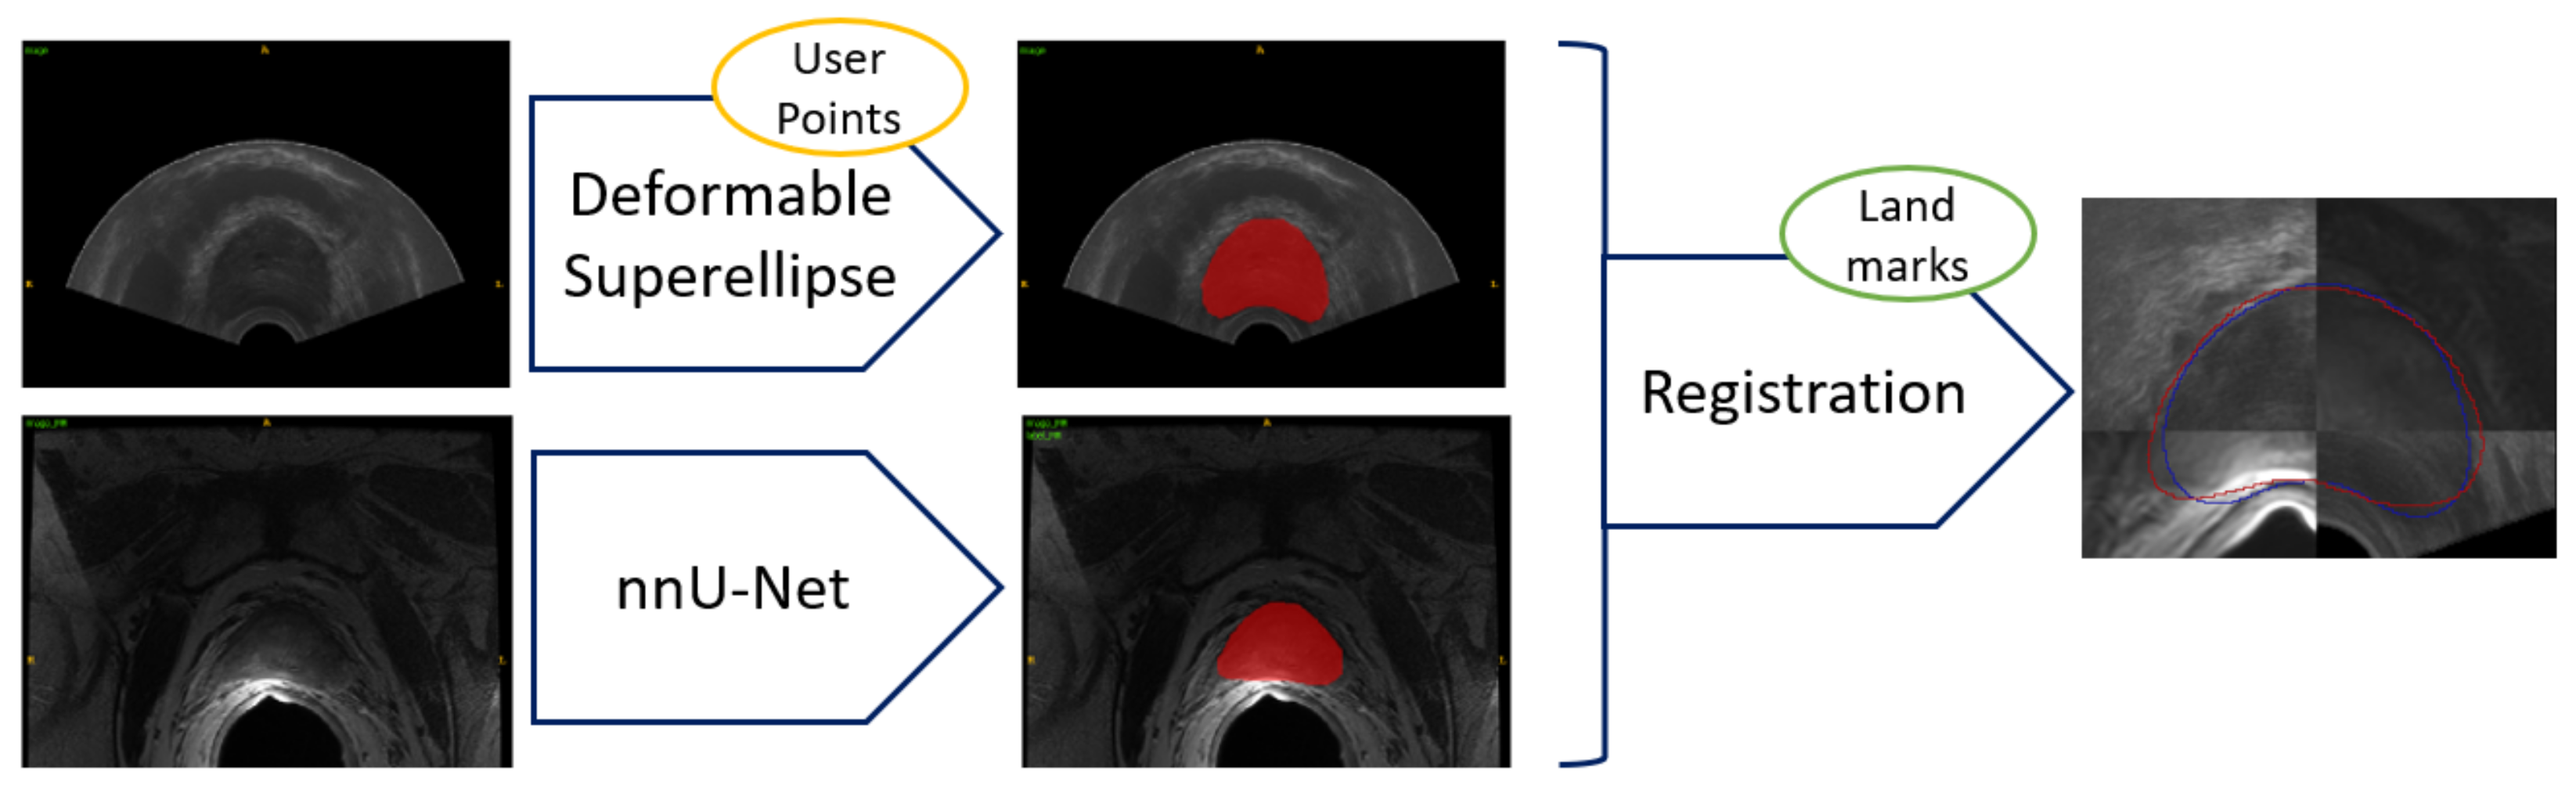

Figure 8.

Results for prostate segmentation from MRI. Top row contains images from the SAML dataset and the second row contains images from ZENODO. The ground truth is represented in red, whereas the predictions from the nnU-Net models are colored in green. The middle image shows the prediction mask for the nnU-Net trained for only 10 epochs, whereas the right image depicts the prediction mask for the one trained on the PROMISE12 dataset.